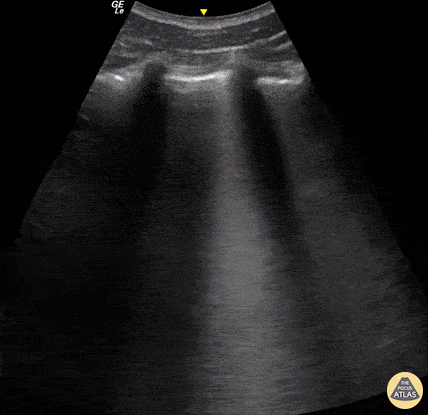

B-Linien =feuchte Lunge, z.B. bei Lungenödem, Infiltrat, Lungenkontusion (Quelle: thepocusatlas.com)

Pneumothorax (rechts bildseitig) mit Lungenpunkt (Quelle: thepocusatlas.com)

Pleuraerguss mit Lungenkonsolidierung (Quelle: thepocusatlas.com)